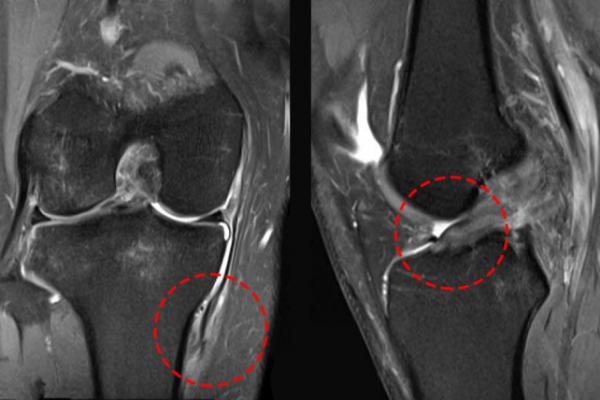

Thạc sĩ, bác sĩ Vũ Trung Hiếu, công tác tại Khoa Chấn thương Chỉnh hình, Bệnh viện Đa khoa Tâm Anh Hà Nội, đã thăm khám cho bệnh nhân Hiệp và phát hiện dấu hiệu dương tính khi thực hiện nghiệm pháp ép vẹo ngoài khớp gối ở góc gấp 30 độ. Đây là dấu…